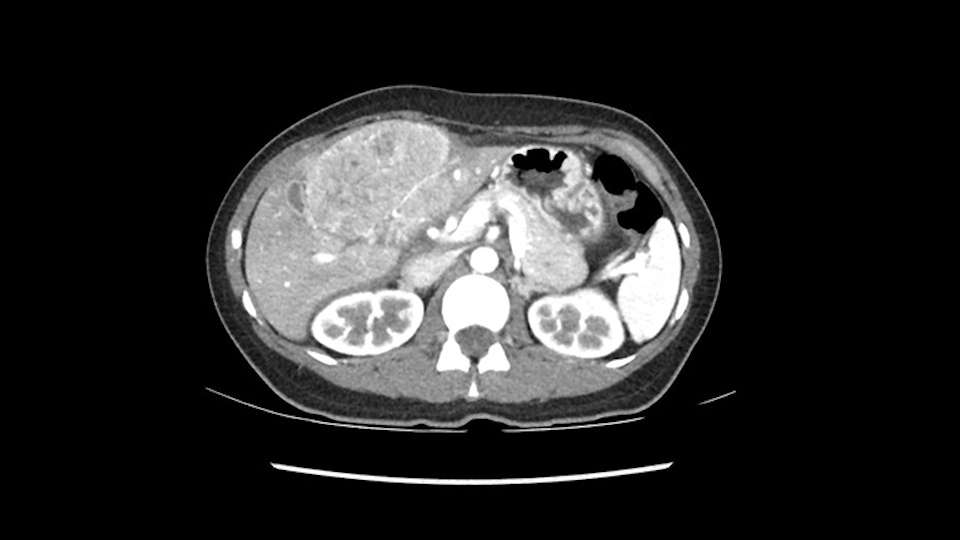

So if we look at the CT scan, on the axial, it’s a larger lesion. It’s about 6 or 7 or 8 centimeters. So it does look a bit threatening in terms of its resectability but if you really drill down deeply into the anatomy, and I think the coronal [imaging] is even better, you can see that the entire mass is on the patient’s left side of the falciform ligament. So it’s really only a left-sided tumor and not even really a left-sided tumor because Segment 4 is uninvolved anatomically.

None of the parenchyma is affected and this tumor is very exophytic; like many Hepatitis B hepatomas; and otherwise is resectable with either a wedge resection part of Segment 2-3 or a formal left lateral segmentectomy.

As I review the CT scan, we have both arterial and venous phases, the tumor is obvious. But I’ll start by saying that the liver itself does not appear to be cirrhotic to my eye. It’s got a normal contour and allied to that, that I do not see evidence of portal hypertension. The spleen is normal, there’s no collateral vessels. The tumor itself, I measured maximally at about 11 centimetres in diameter and I’m told the alpha fetoprotein is very high (over 10000), which is entirely consistent with this being a solitary hepatocellular carcinoma that is very exophytic. It seems to emanate off the inferior margin of Segment 3 (because that’s the falciform). I’ll start by saying that this is not transplantable. The tumor exceeds our guidelines for transplantation, but it's likely resectable based on normal liver and no portal hypertension.

So the issue with regards to resection. A left sided tumor. I believe I can see the falciform ligament right here so we’re looking at a resection of Segments 2, 3 of the left lobe of the liver. The left portal vein is right there. I think we’ll be wiser to take the left portal vein and therefore get well into Segment 4 and do a left hemihepatectomy. Certainly, one does not need to take the middle hepatic vein; it’s miles from the tumor.

Hi my name is Sedat Karademir. I’m from Ankara Guven Hospital and I’m an HPB and transplant surgeon. We are discussing about the case I reviewed the CT of 41 year old lady with a suspected hepatoma in the left lateral segment. Presumably its Segment 3. It looks like a big tumor sitting exophytically mostly out of the liver and pressing on the surrounding organs, but it doesn’t look like any invasion there. In this situation, according to the venous and arterial anatomy, it looks like this will be a Segment 2 and 3 resection.

The tumor is so close to the falciform ligament, I had a question mark about the Segment 4b relation between segment 4b and segment 3. In a normal resection of segment 2 and 3, we would be keeping on the left side of the falciform ligament and start getting segment 3 and 2 portal pedicles but in here its getting so close. So oncologically, 4b should be checked during the OR.

When you see the axial sections of the scan, you find it's a largely exophytic mass and its well-encapsulated. So this is typically true of a well-differentiated hepatocellular carcinoma. If you look at this, this is the gallbladder which is being displaced to the right and the mass is in the Sg4 of the liver, exophytic, projecting down. As it is coming down, it is also displacing the duodenum and the head of the pancreas which is being pushed towards the left and it's going right up to the cava, the start of the anterior surface of the cava. Obviously getting a lot of collaterals and vascularity from all the vessels around but one has to be very careful in evaluation of the main portal pedicle in this particular case and of course arterial inflow to the Sg4 and of course the left lobe of the liver.

What kind of procedure can we plan for this patient? It obviously has to be a left hemihepatectomy because most of the lesion is actually in Sg4. Can we do something which is less than a hemihepatectomy and just do only a segmental resection? The answer to that is that this vascular supply, if you are trying to ligate only the portal venous pedicle to the Segment 4, it is very close to the tumor and you will end up not having not a great margin as far as tumor resection is concerned so I would recommend a left hemihepatectomy and not just a partial or segmental resection. You can also see that it is crossing the falciform line and going on to Segment 2 and 3 so trying to do anything less than a left hemihepatectomy may not give the right kind of margins which we need for this tumor. Fortunately for us, the contours of the liver, which are very important to see in a Hepatitis B patient, there are no cirrhosis which I can see. The normal liver functions indicate that it's a well compensated Hepatitis B.

My name is Gonzalo Sapisochin. I’m an assistant professor of surgery at the University of Toronto and a hepatobiliary and pancreatic surgical oncologist here at the University Health Network. So this patient has a big mass, likely growing from the left lobe of the liver, around 9-10 cm.

So in planning for this operation, as I look at the scans, I first visualize the arterial phase and I can see that there’s are a lot of big feeding arteries to this large tumor. Likely all the right side vessels feeding the right side of the liver: right hepatic artery and likely the Segment 4 artery are spared from the tumor. It’s likely the left hepatic artery is ramificating and giving feeding arteries to this tumor. It certainly looks like a large mass that its compressing other structures like the cava, the pancreas, the stomach; but I think there’s a plane and we can see that better in the venous phase. There’s a plane of separation between the gallbladder, the pancreas, the cava, that this tumor is abrupting but likely not invading. Usually, these masses actually don’t invade at that level and basically are pushing the tissues and once you open, you’re able to separate the tumor. Sometimes there’s some adhesions but you can actually separate and there’s usually no invasion.

The other thing I would do in this case is to certainly to assess the coronal phase as we can see in the coronal phase, this tumor looks like it's growing from Segment 3, and again I don’t think there’s involvement of the right side of the liver or even on Segment 4.